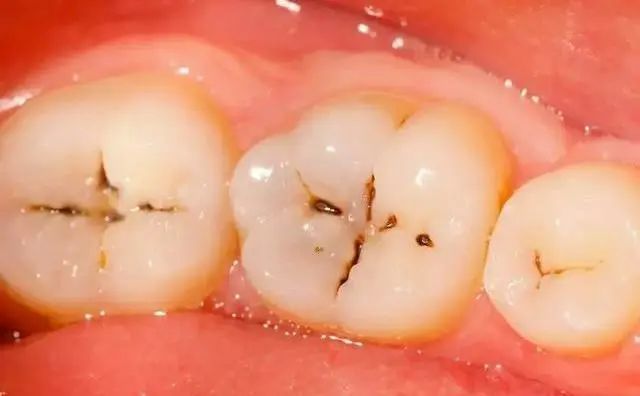

第一阶段——浅龋:

牙齿咬合面有黑线,大牙一般最常见,说明开始蛀牙了,牙釉质被细菌龋坏,但不痛不痒,会出现窝沟龋得及时补牙,而不是去洗牙;

第二阶段——中度龋:

牙齿出现小黑洞,说明引起中度蛀牙,细菌腐蚀来到牙本质,伴随着牙齿敏感,黑色腐败物质其实就是细菌的产物,这时候还可以再补牙;

第三阶段——深龋:

牙齿超过一半烂掉,说明已经重度蛀牙,细菌伤及牙髓牙神经,还伴随着剧烈疼痛,牙神经病变这时得根管治疗处理,挽救伤痕累累的牙齿。